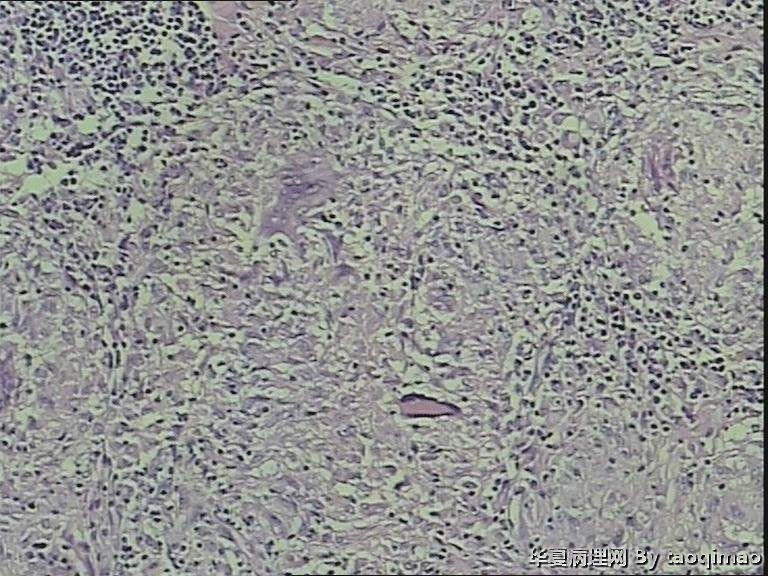

颈部淋巴结

• 颈部淋巴结图1

图1

刘秀敏女55岁,发现左颈肿物一年,质韧活动度差,无压痛。

粉红色球形肿物,1.7x1.5x0.7cm,包膜完整切面灰黄,质韧。

肉芽肿性炎  抗酸染色

淋巴结肉芽肿性病变,考虑结核的可能性大,做抗酸染色/PCR/联系临床

肉芽肿性炎,考虑结核

肉芽肿性炎,考虑结核。做个抗酸看看。

结核与结节病间鉴别

淋巴结结核